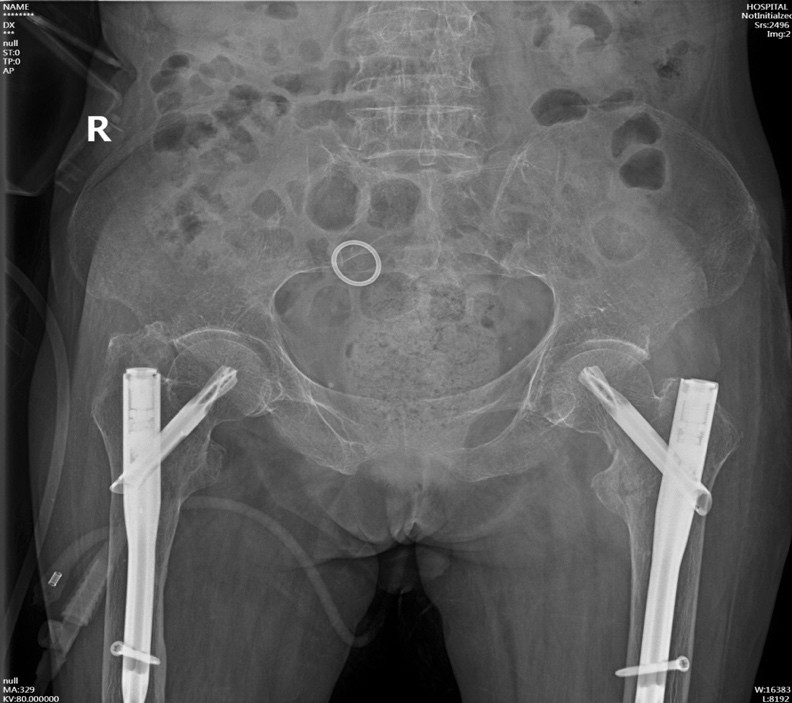

手术在病人骨折后第三天实施,手术当天在麻醉科王翔峰主任团队的紧密协作,修忠标主任医师的指导下,钟水林主治医师和韩海医师顺利地完成了手术,手术总共耗时30分钟。

由于患者内科基础疾病较多,为保障其安全,术后将陈奶奶转移至ICU病房进一步治疗。在ICU监护期间,陈奶奶出现反复发热、循环不稳等情况,在重症医学科李红艳主任医师的指导下,制定了相应的治疗方案。陈奶奶的各项生命体征逐渐稳定,后转回我科继续治疗。

从ICU转回我科后,发挥黄播 中医特色,运用中医药对病人进行身体调理。在潘玮护士长带领的护理团队精心护理下,陈奶奶的精神状态也一天天好起来。

如今,陈奶奶精神状态渐佳,生活能自理,已顺利出院,陈奶奶的家属对此非常感激。